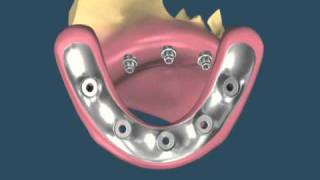

Perguntas frequentes sobre Implantodontia

1. Quanto tempo preciso ficar afastado do meu trabalho para fazer os implantes? A cirurgia de implantes normalmente tem um pós-operatório...

10 MOTIVOS PARA FAZER UM IMPLANTE DENTÁRIO

1 – Autoestima O motivo que leva muitas pessoas a buscarem um tratamento de implante dentário: Perder um dente tira a autoestima de...

Diga adeus as dentaduras, ponte-móveis e ponte-fixas - Implantes Dentários a solução

Medo de Implante? Entenda o que é e como funciona! Cada dia mais procurados, os implantes devolvem, literalmente, o sorriso dos...